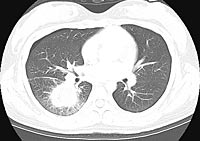

A CT SCAN was done and selected cuts are seen

below.

WHAT IS YOUR INTERPRETATION?